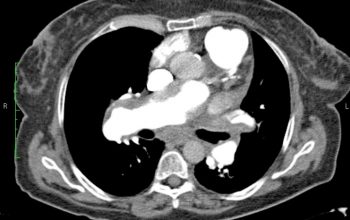

Το ενδοβρογχικό υπερηχογράφημα είναι μια σχετικά νέα διαγνωστική τεχνική που μπορεί να χρησιμοποιηθεί για τη διερεύνηση βλαβών στους πνεύμονες ή στην περιοχή του θώρακα και μεταξύ των πνευμόνων. Πρόκειται για μια δύσκολη περιοχή για να απεικονιστεί και αυτό που κανονικά γίνεται με τη χρήση ενός συνδυασμού των ακτίνων Χ, αξονικής τομογραφίας και βρογχοσκόπησης, μπορεί να επιτευχθεί με το ενδοβρογχικό υπερηχογράφημα (τρεις εξετάσεις σε μία). Μέχρι πρόσφατα, προκειμένου να επιτευχθεί μια αξιόπιστη διάγνωση φυματίωσης, λεμφώματος, σαρκοείδωσης ή καρκίνου πνεύμονα χρειαζόταν παρακολούθηση του ασθενούς ή μια επεμβατική βιοψία στο χειρουργείο. Σήμερα μπορούμε να έχουμε μια βρογχοσκόπηση με ενδοβρογχικούς υπερήχους, όπου θα παρθούν στοχευμένα δείγματα ιστού από το σημείο της βλάβης και θα έχουμε αποτέλεσμα άμεσα από ταχεία βιοψία χωρίς να χάνουμε πολύτιμο χρόνο στη διάγνωση και αντιμετώπιση της ασθένειας. Πρόκειται για μια εξαιρετικά αξιόπιστη εξέταση που πραγματοποιείται ταχύτατα (30 λεπτά) και με ασφάλεια.

- Όταν η αξονική τομογραφία θώρακος αποκαλύπτει ότι ορισμένοι από τους λεμφαδένες στο κέντρο του στήθους είναι διογκωμένοι. Αυτό μπορεί να είναι ένα σημάδι του καρκίνου του πνεύμονα ή σαρκοείδωσης, φυματίωσης ή λεμφώματος.